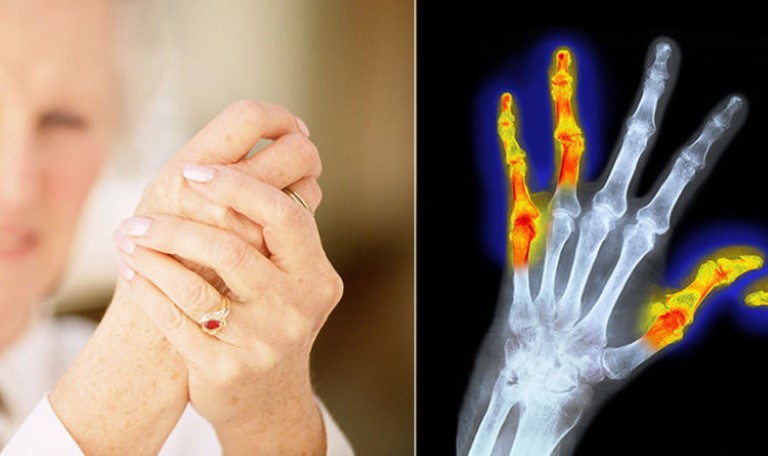

Bệnh phong thấp là một trong những căn bệnh phổ biến và nó xảy ra nhiều đối với người cao tuổi, những người lao động nặng nhọc hay những người phải ngồi lâu và ngồi nhiều.

Theo Đông Y bệnh phong thấp thuộc phạm vi chứng tý, do phong, hàn, thấp xâm nhập vào cơ thể đang bị suy yếu và nó gây ra những tổn thương đối với huyết mạch, cơ xương khớp và tim... Còn trong Tây Y, phong thấp chính là tên gọi khác của bệnh viêm khớp dạng thấp và nó có liên quan tới hệ miễn dịch trong cơ thể.

Người bị phong thấp cần phải đặc biệt lưu ý tới chế độ ăn uống của mình. Trong đó, theo các bác sĩ, người bệnh phong thấp không nên uống nước dừa. Bởi nước dừa có tính mát, hàn và khi bổ sung vào cơ thể sẽ khiến từng trạng đau nhức của bệnh ngày càng nặng hơn.